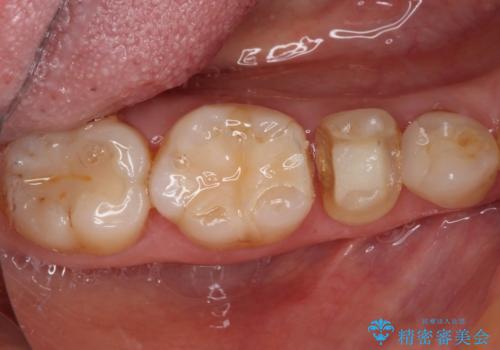

- 他院にて治療した詰め物が欠けてしまった事を主訴に来院された患者様です。

詰め物の範囲が大きく、部分的な詰め物では再び割れてしまうリスクが高いため、

オールセラミッククラウンにて補綴することとしました。